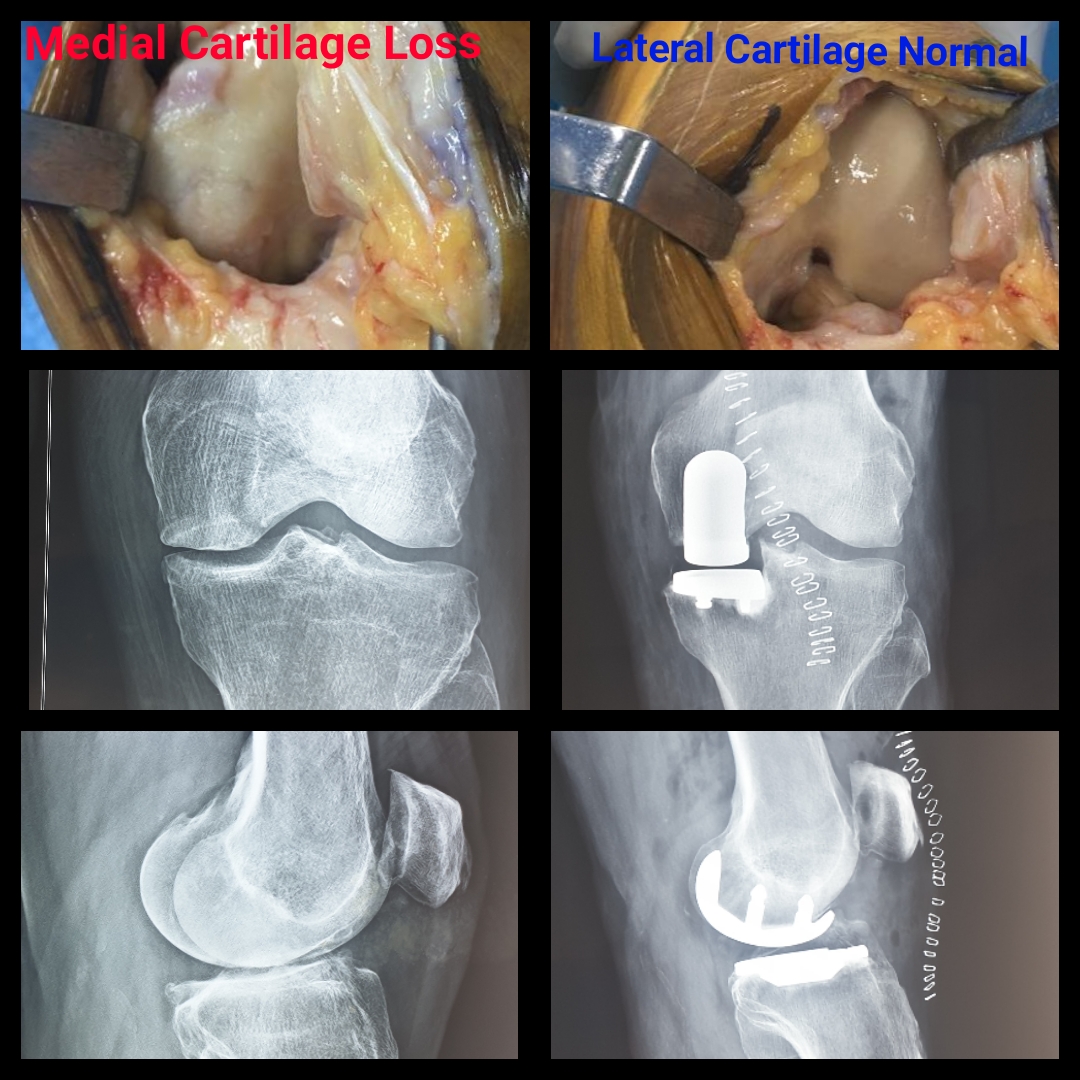

Read MoreHistory: 85-yr-old patient on whom Partial Knee Replacement was performed by Dr. Amyn Rajani Case: A lot of patients and doctors ask Dr. Amyn Rajani why Partial Knee Replacement instead of Total Knee Replacement for elderly. Look at the lateral…

Read MoreWould you replace all four tyres for only one deflated tyre? Then why do that to your knee? In Osteoarthritis most of the wear and tear happens on the inner side of the Knee and with a Partial Knee Replacement,…